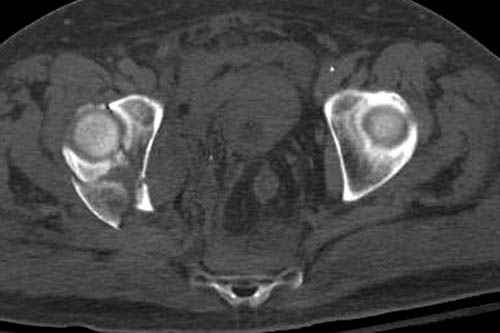

Наш недавний случай перкутанной фиксации "методом

Сиэтла" спицами 2.8 мм с резьбой на конце.

Извиняюсь за качества снимков, обычный больной в 300 фунтов, портативным ренген аппаратом не пробить.